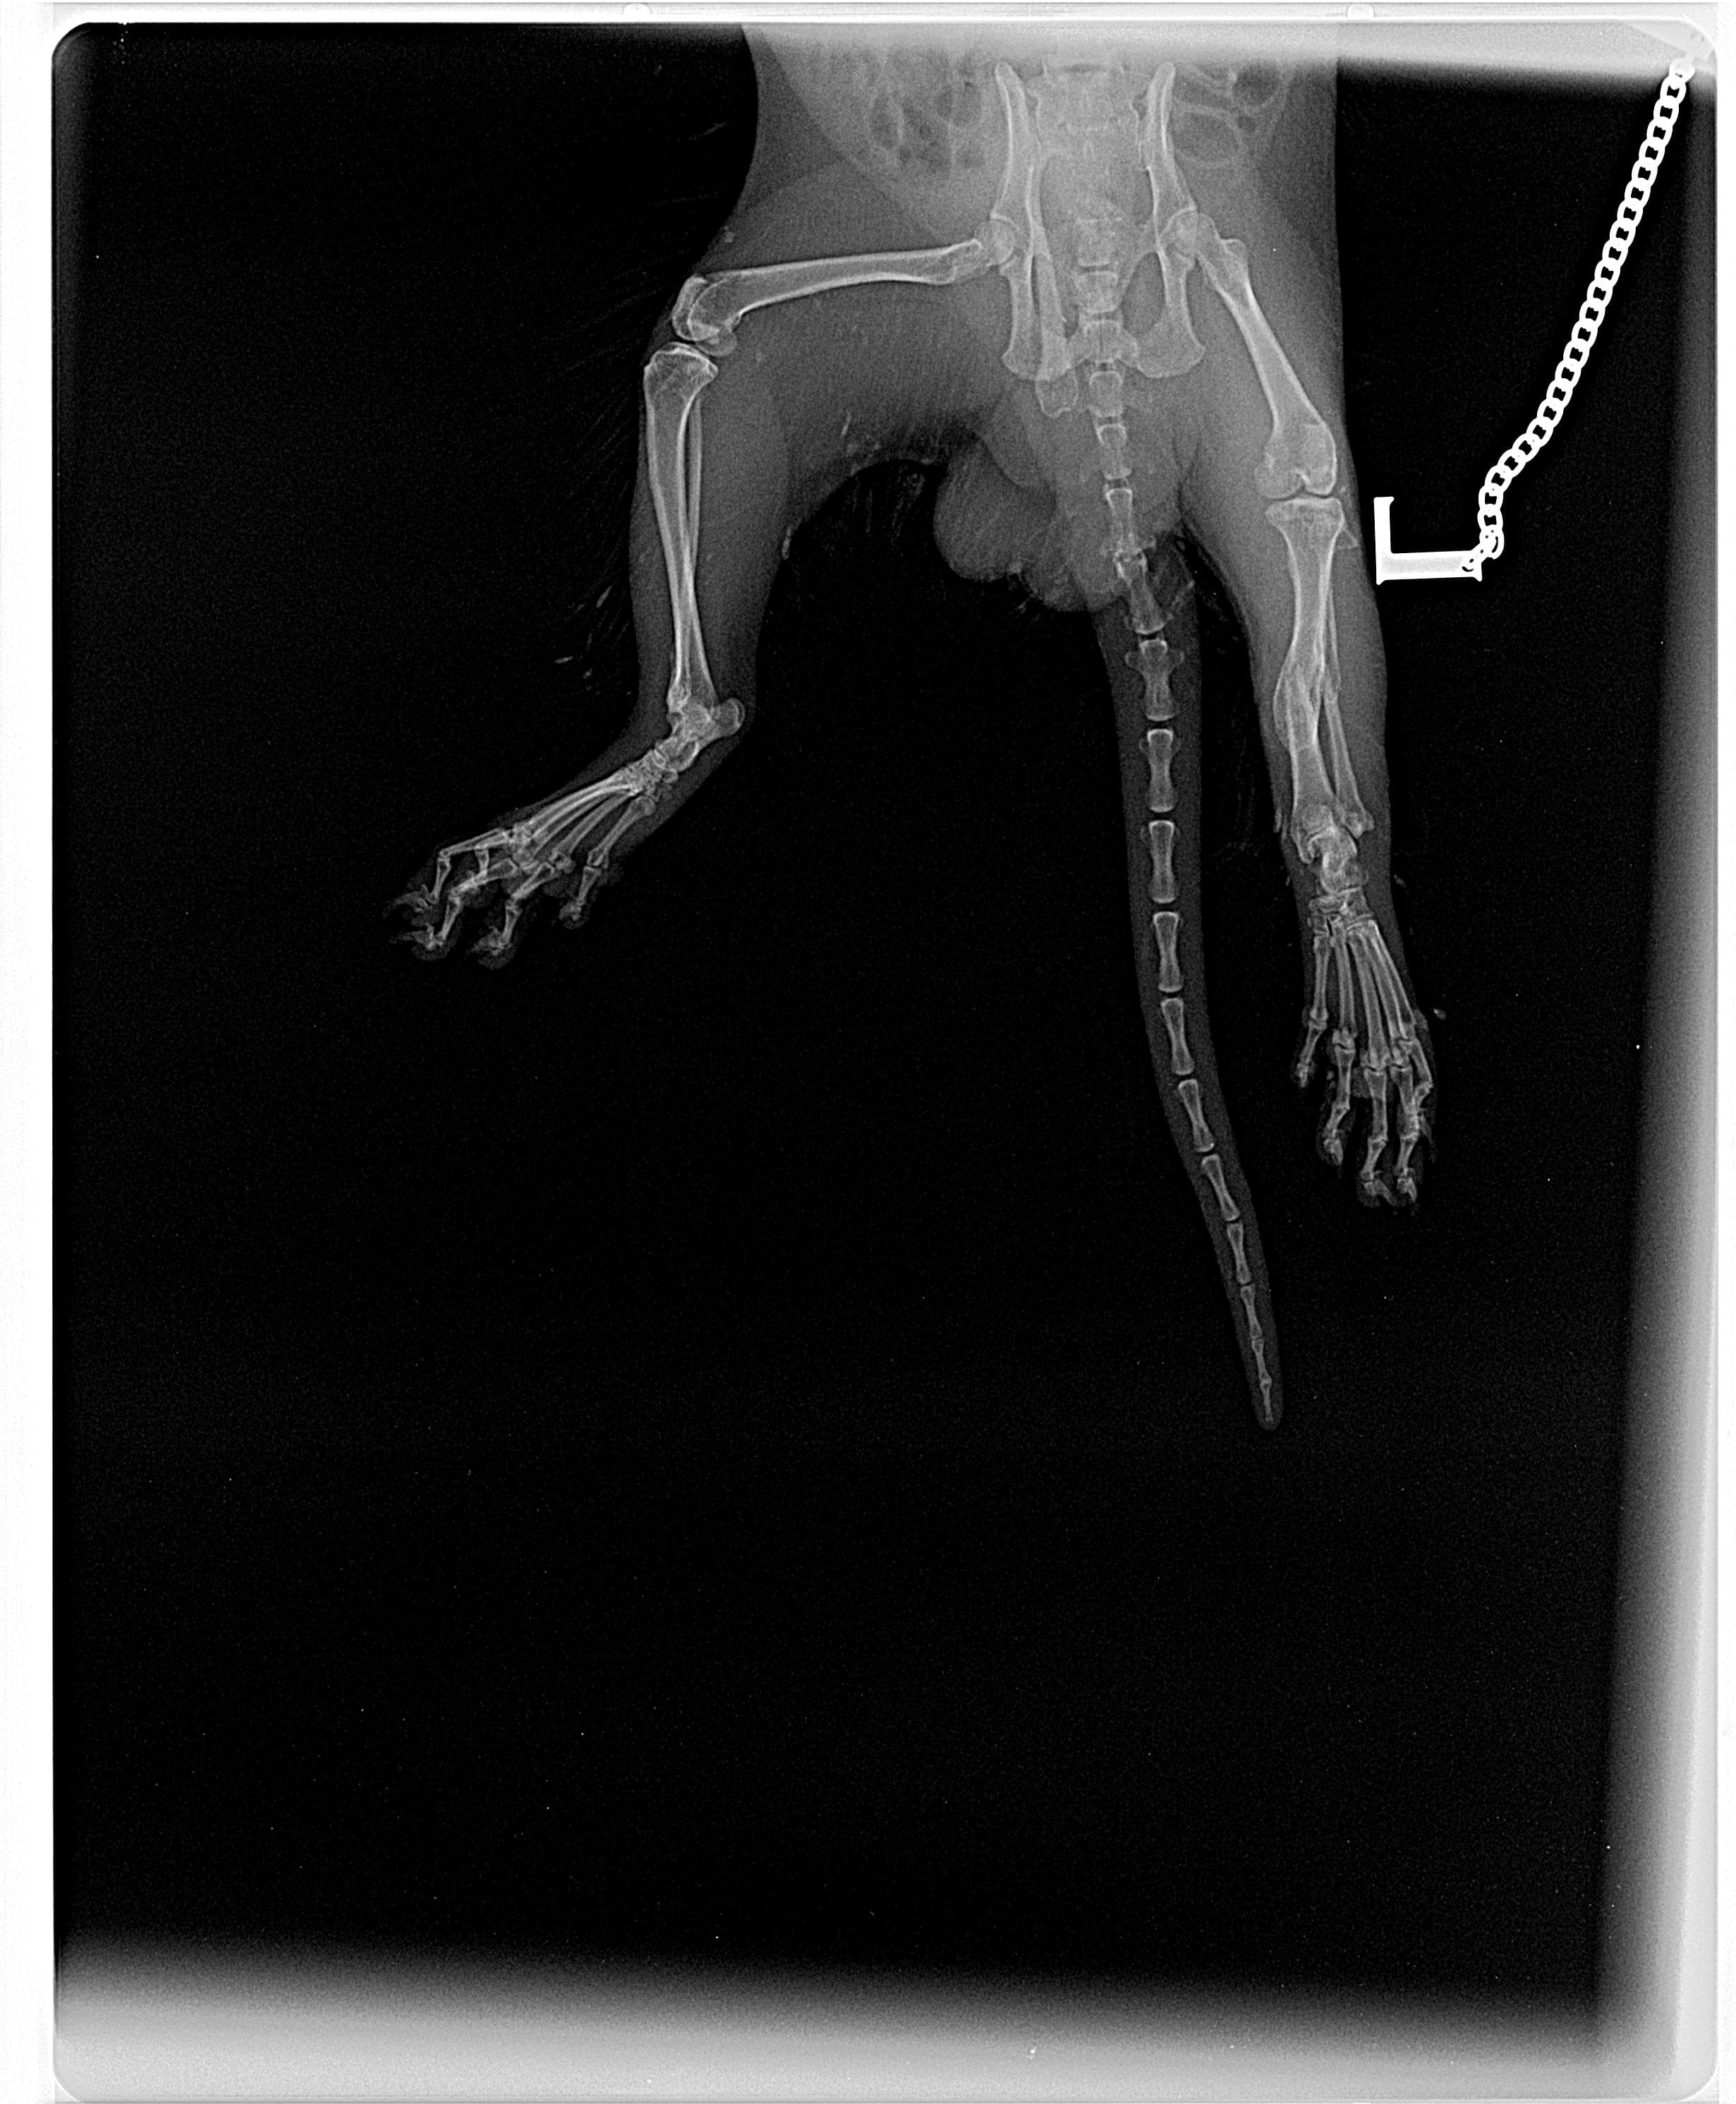

Hello, i have attached an xray done by pdsa sunderland who say my friends ferret has not got a broken leg...would appreciate and value your opinion because it looks broken to me, many thanks, Dave

Looking at the xray the ferret had a broken leg a while ago which has mended itself. At this time it is not broken but it is a bad mend and the leg is likely shorter than the other one. Unless the ferret is in pain or the leg is swollen, there is no need to fix that. If the ferret has pain or other problems due to the old fracture and the callus around it, it will likely need surgery to rebreak it and then fix the leg properly. It would be necessary to have one or two more views from a different angle as this could also be an osteosarcoma lesion (bone cancer) which would need to be investigated.